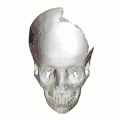

- Animation. Left parietal bone removed. Squamosal sutures shown in red.